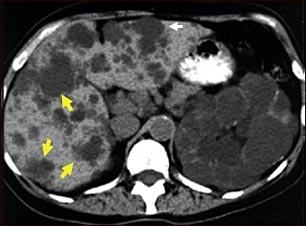

Quistes del riñón y el hígado; TC

Esta TC abdominal muestra quistes en el hígado y los riñones (enfermedad poliquística). El hígado es el órgano grande situado en la parte izquierda de la pantalla. Las manchas oscuras sobre el hígado son los quistes.